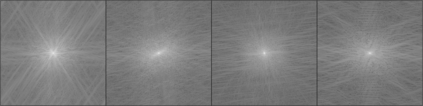

Objectives: Present a novel deep learning-based skull stripping algorithm for magnetic resonance imaging (MRI) that works directly in the information rich k-space. Materials and Methods: Using two datasets from different institutions with a total of 36,900 MRI slices, we trained a deep learning-based model to work directly with the complex raw k-space data. Skull stripping performed by HD-BET (Brain Extraction Tool) in the image domain were used as the ground truth. Results: Both datasets were very similar to the ground truth (DICE scores of 92\%-98\% and Hausdorff distances of under 5.5 mm). Results on slices above the eye-region reach DICE scores of up to 99\%, while the accuracy drops in regions around the eyes and below, with partially blurred output. The output of k-strip often smoothed edges at the demarcation to the skull. Binary masks are created with an appropriate threshold. Conclusion: With this proof-of-concept study, we were able to show the feasibility of working in the k-space frequency domain, preserving phase information, with consistent results. Future research should be dedicated to discovering additional ways the k-space can be used for innovative image analysis and further workflows.